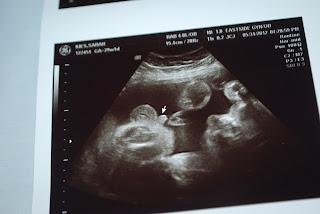

28 weeks

Even though I am now almost 32 weeks we did get an ultrasound when I was 28 weeks. Little man is doing well and is right now estimated at 3 pounds 1 oz. The last ultrasound picture is a 3d of his face and you can already tell that he looks like our girls. We are looking forward to meeting him Aug 10th when I get induced.